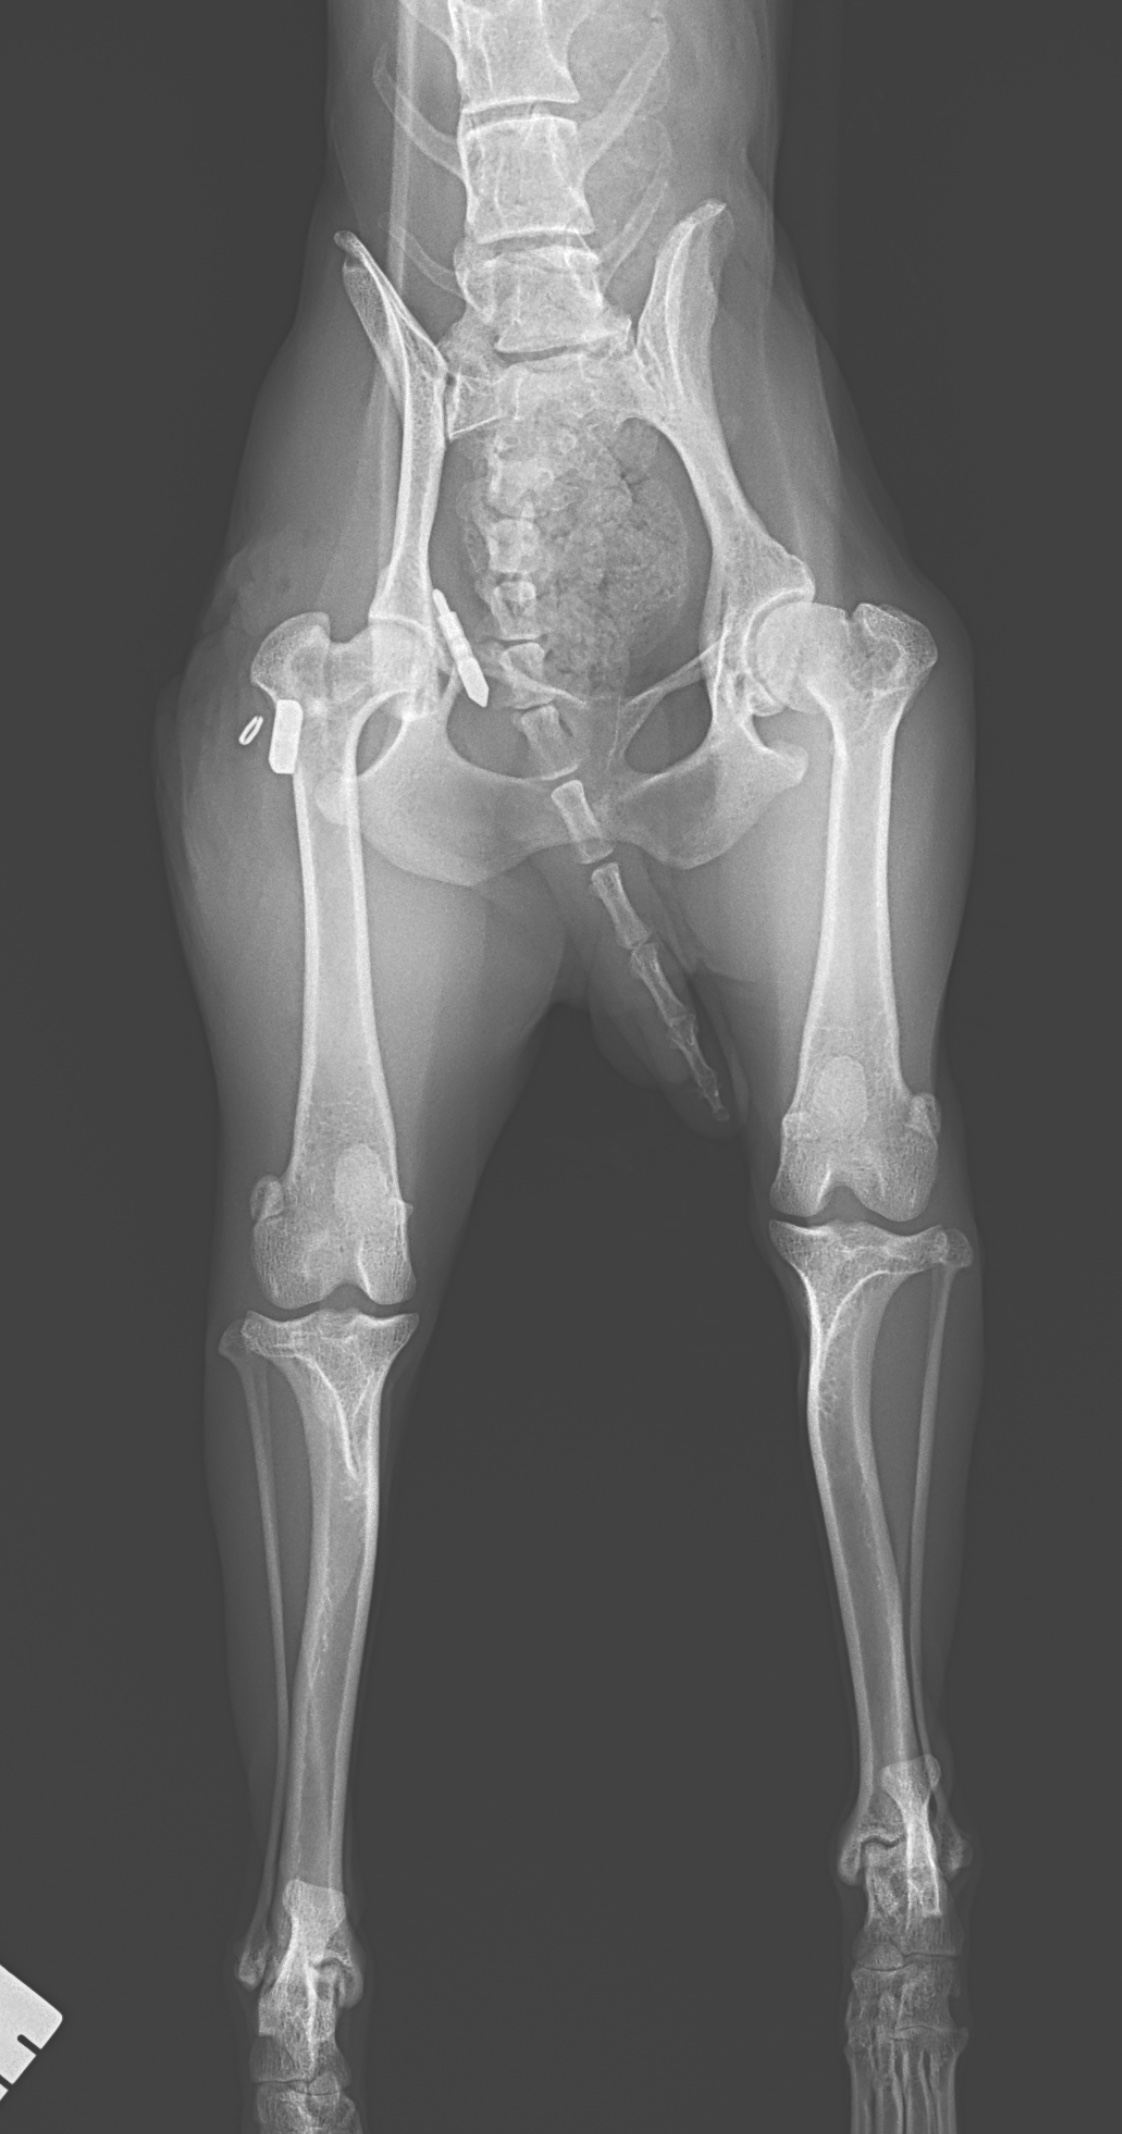

股関節脱臼に対するトグルロッド #62

トイ・プードルが室内で転倒し、股関節脱臼を起こしたとのこと。失われた股関節機能を取り戻すために、大腿骨頭靭帯をもっとも生理的な方法で再建する”Toggle Rod法”で対応しました。シンプルかつ短時間で施術が可能です。外側アプローチ、寛骨臼にφ2.5の骨孔を形成。2.4砲弾型トグルロッドにポリエステル縫合糸を装着し、寛骨臼内の骨孔に刺入する。大腿骨頭側より骨頭靭帯付着部位から第3転子に向け2.0のボーントンネルを作成。第3転子側よりパッサーでスーチャーリレーし、エンドボタンで第3転子に締結。”適応症例の選択さえ間違えなければ、誰がやっても成功率の高い治療成績が担保されている”。そういった術式こそ本当に必要とされる術式です。しかしながら、再脱臼(20%)は2週間以内に起こることが知られているので、術後しばらくは安静が必要です。